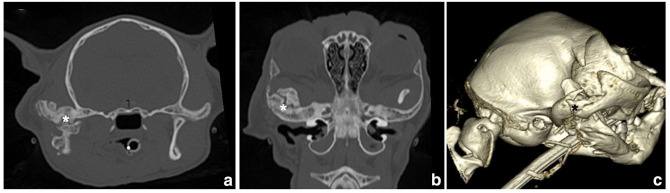

Case summary: A 1-year-old spayed female domestic British Shorthair cat was presented for facial trauma; there were multiple mandibular fractures involving the right temporomandibular joint (TMJ) that were managed conservatively. After 2 months, the owner reported a gradual onset of the cat's inability to open its mouth and subsequent inappetence. The maximum mouth opening (MMO) measured 7 mm. CT showed ankylosis of the TMJ, and surgical treatment with caudal segmental mandibulectomy (CSM) was performed. The cat had a rapid postoperative recovery and returned promptly to spontaneous eating, with a nearly normal MMO of 33 mm. A CT scan performed 3 months postoperatively showed a mild rightward deviation of the mandible, and a clearly visible non-ossified ostectomy gap between the body and the ramus of the right mandible. The cat continued to eat spontaneously without dysphagia following surgery and was asymptomatic 1 year postoperatively.

Relevance and novel information: To the authors' knowledge, this is the first report describing the tomographic findings after CSM, as compared with the clinical outcome. Postoperative CT is indicated to confirm the success of the procedure and to assess TMJ ankylosis sequalae or complications of the CSM surgical site at an early stage. This report confirmed the effectiveness of CSM in resolving TMJ stiffness due to articular fractures or ankylosis with a good clinical and tomographic outcome.